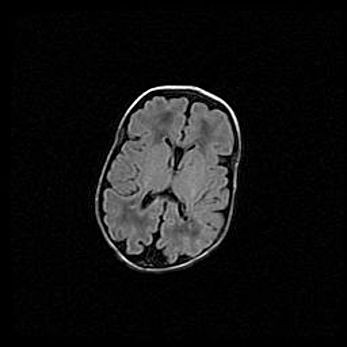

Сообщающаяся гидроцефалия. Кистозная энцефаломаляция головного мозга.

Возраст: 3 месяца 4 дня

Вес: 3100 г

Пол: женский

Окружность головы: 34 см

Срок гестации: 31 неделя

Кистозная энцефаломаляция головного мозга - одна из форм поражения головного мозга в детском возрасте. Характеризуется возникновением множественных и распространённых кист в коре, белом веществе и подкорковых образованиях головного мозга у плодов, новорождённых и детей раннего возраста. Развитие кистозной энцефаломаляции связано с внутриутробной асфиксией и гипотонией, родовой травмой, тромбозом синусов, пороками развития сосудов, инфекциями, сепсисом и другими причинами. Наиболее значимые инфекционные агенты: вирусы простого герпеса, цитомегалии, краснухи, токсоплазмы, энтеробактерии, золотистый стафилококк и другие.